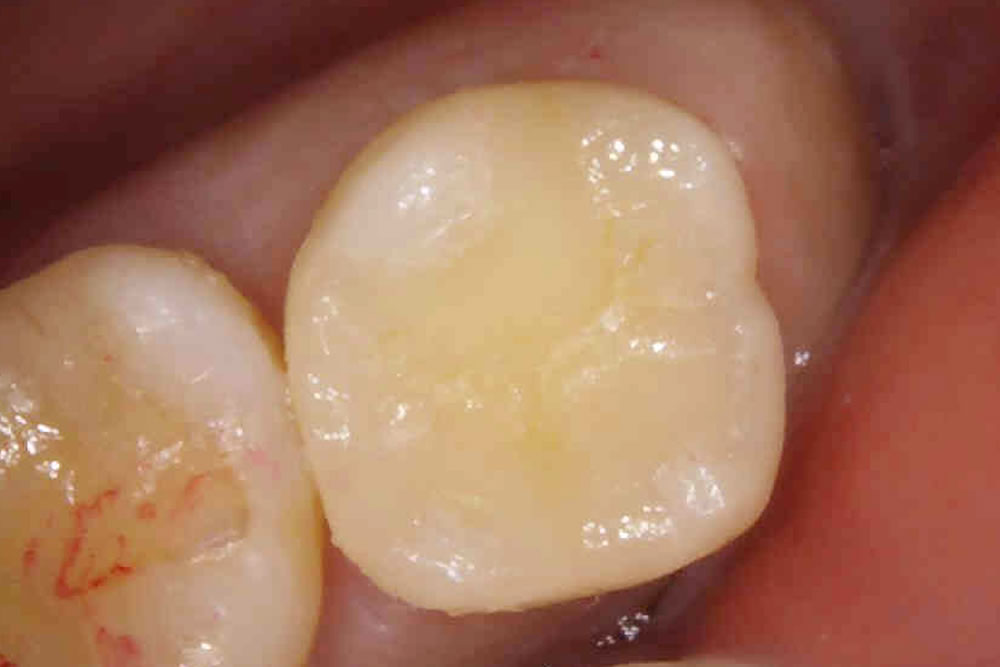

セラミックインレーの装着・治療完了

完成したセラミックインレーを装着し、咬み合わせを調整して治療完了です。

セラミック治療では、色を患者さまの歯の色に合わせてお作りすることが出来るので、より自然な仕上がりになります。

治療後は治療前と変わらず問題なく噛むことができ、大変満足していただいております。